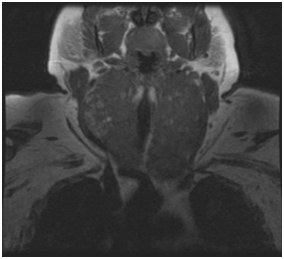

Figure 1 MRI demonstrating goiter extending under aortic arch.

6. A higher frequency of recurrent laryngeal nerve injury was noted in cancer cases due to tumor invasion (Figures 1-6)